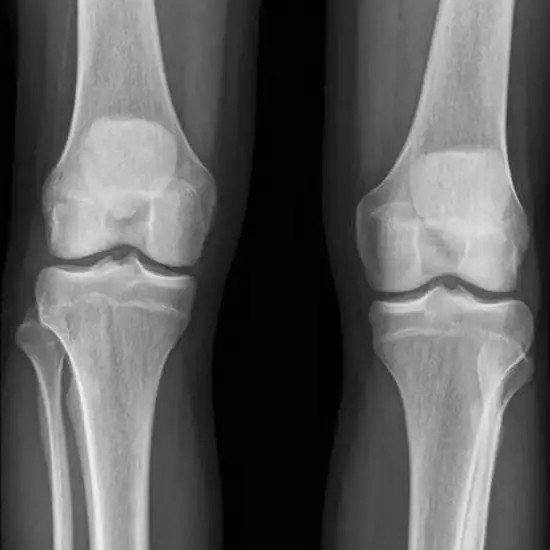

X-Ray bilateral knee AP (anteroposterior) standing View is a non-invasive procedure, that uses an x-ray beam placed in front of the patient to evaluate both knee joints to diagnose the underlying problems. Doctors recommend this procedure to diagnose the alignment problem, quality of bones, knee disorders as well as degenerative changes in both knee joints.

Doctors recommend the procedure of X-Ray bilateral knee AP (anteroposterior) standing View if the patient experiences the symptoms of knee problems such as knee pain, inflammation, tenderness, swelling, etc.

• To detect the extent of degenerative changes within both knees.

• Osteoarthritis and other knee disorders